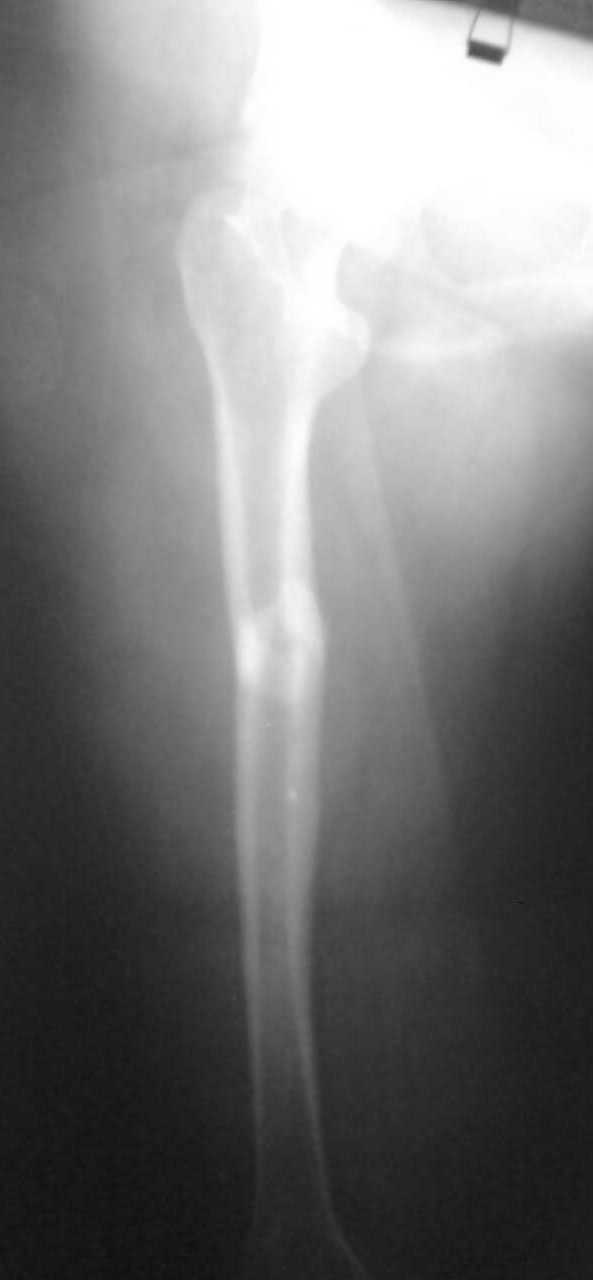

Перелом поперечный с незначительным смещением и с захождением отломков около 2,0см. Перелом типа А 1.